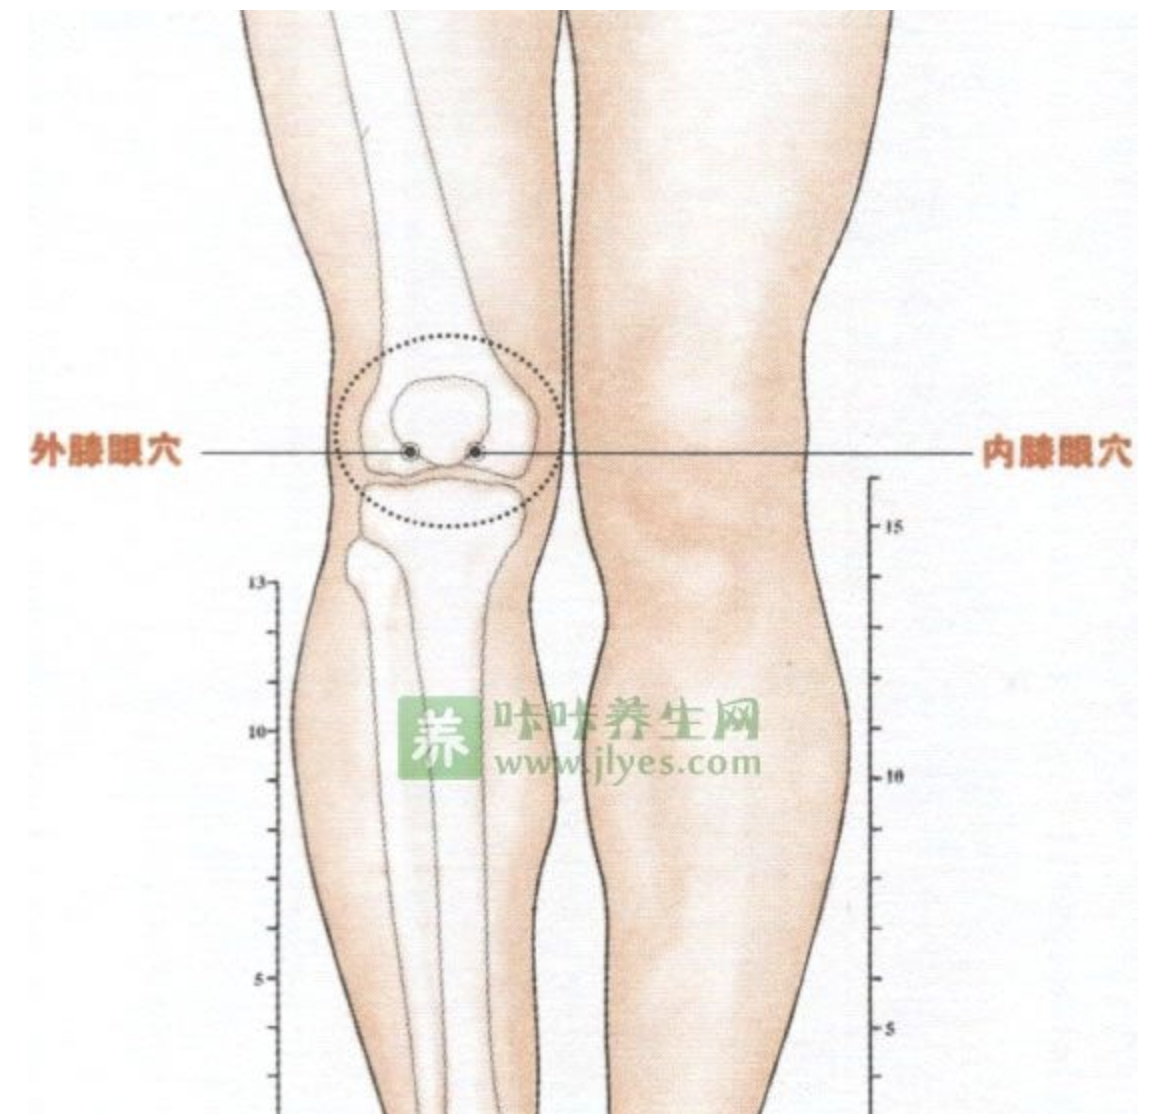

膝眼

【定位】 屈膝,在髌韧带两侧凹陷处。在内侧的称内膝眼,在外侧的称外膝眼。

【主治】 膝痛,腿痛,脚气。

【刺灸法】 向膝中斜刺 0.5 ~ 1 寸,或透刺对侧膝眼;可灸。